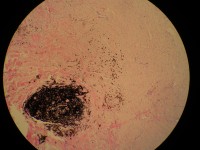

性别年龄33岁临床诊断皮肤色素痣

一般病史左上肢皮肤有一0.3CM 灰黒区,略高与皮肤。

大体所见小块不规则形带皮组织一块,大小0.6*0.5*03CM,皮肤表面中心部可见一0.3CM灰黒区。

镜下见一黒色巢团色素细胞,其周边纤维组织中可见散在色素样细胞

考虑深部穿通性痣

是兰痣,要鉴别陈旧性出血。

普通型蓝痣,组织平切了

复合痣不排除。